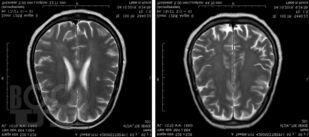

В руководстве представлены сведения о редко встречающихся (в том числе орфанных) неврологических синдромах и болезнях, сгруппированных в 4 главы в зависимости от этиологии: аутоиммунные и воспалительные; врожденные пороки развития нервной системы, наследственные и дисметаболические; опухоли нервной системы и паранеопластические синдромы; нейродегенеративные заболевания. В отношении каждой болезни представлены эпонимические сведения, шифр по МКБ-10, эпидемиология, этиология, патогенез, патоморфология, клиническая картина, диагностика, дифференциальная диагностика, лечение и прогноз. Все разделы книги иллюстрированы собственными клиническими случаями и результатами их обследований.